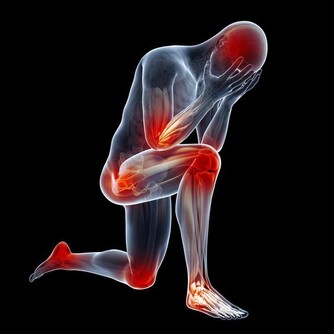

肝臟不好的人,還會出現這些表現

1、皮膚出油,皮膚乾燥,頭髮容易出油

2、背部長大量粉刺,且背部容易出油

3、面色發黃,體形消瘦,牙齦出血

4、尿液發黃,尿液起沫,鞏膜發黃

5、眼睛乾澀,早晨起床眼屎多

6、食慾不振,腸胃消化不良,經常便秘

7、面色發黑,身體出現蜘蛛痣,肝掌